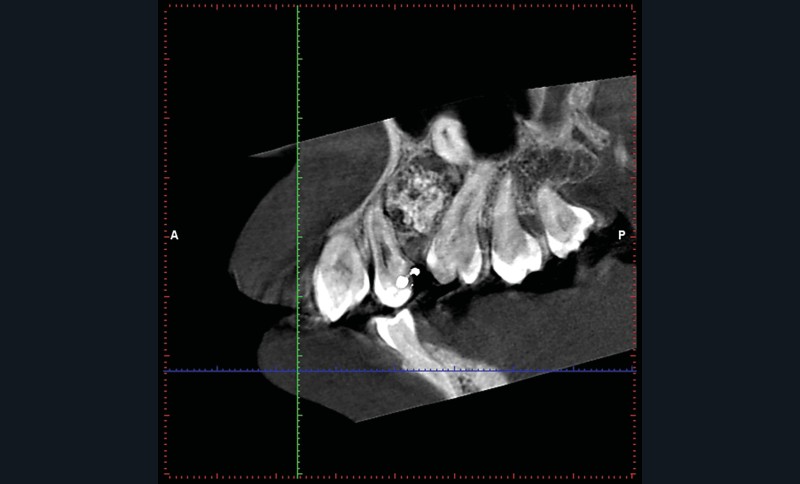

Un CBCT est pratiqué : la périphérie de la lésion ne présente pas de réaction ostéoclérotique (fig. 2) et on retrouve un liseré radioclair « ceinturant » la lésion (fig. 3).